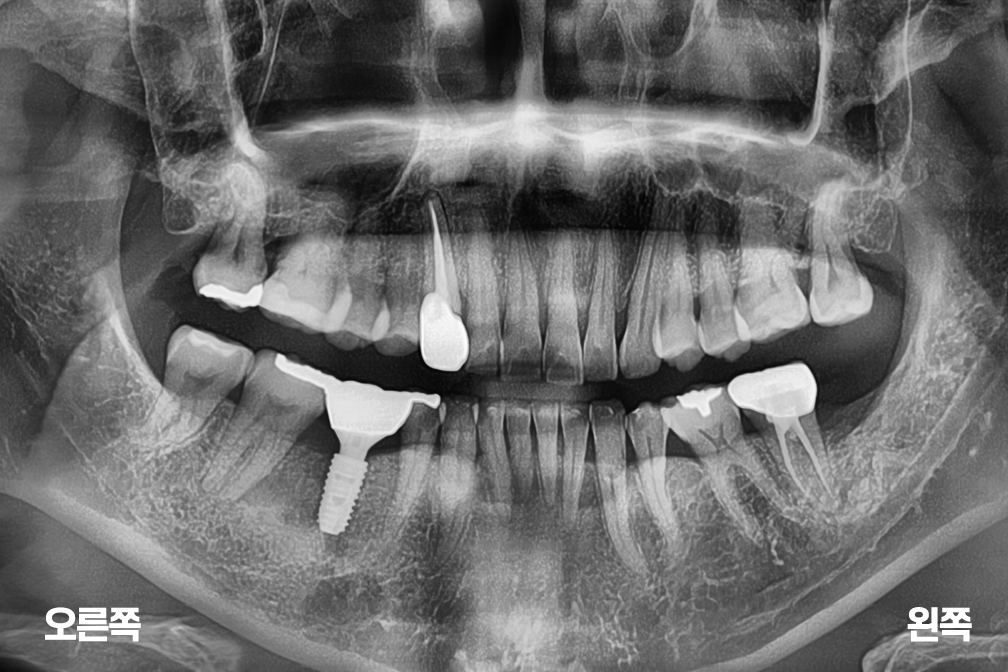

임플란트 오른쪽 아래 어금니 임플란트 수술

어금니 임플란트

Before 2025년 5월 16일

After 2026년 1월 16일

위 전후사진은 이미지사진으로 실제 눈으로 보는 것과는 다를 수 있으며, 환자의 치아상태과 방법에 따라 치료결과가 다를수 있습니다.

사진의 날짜는 촬영날짜이며 치료의 기간이 아님을 알려드립니다.

치료 후 치아표면의 탈회 , 충치, 치근흡수 등의 부작용이 있을 수 있습니다.